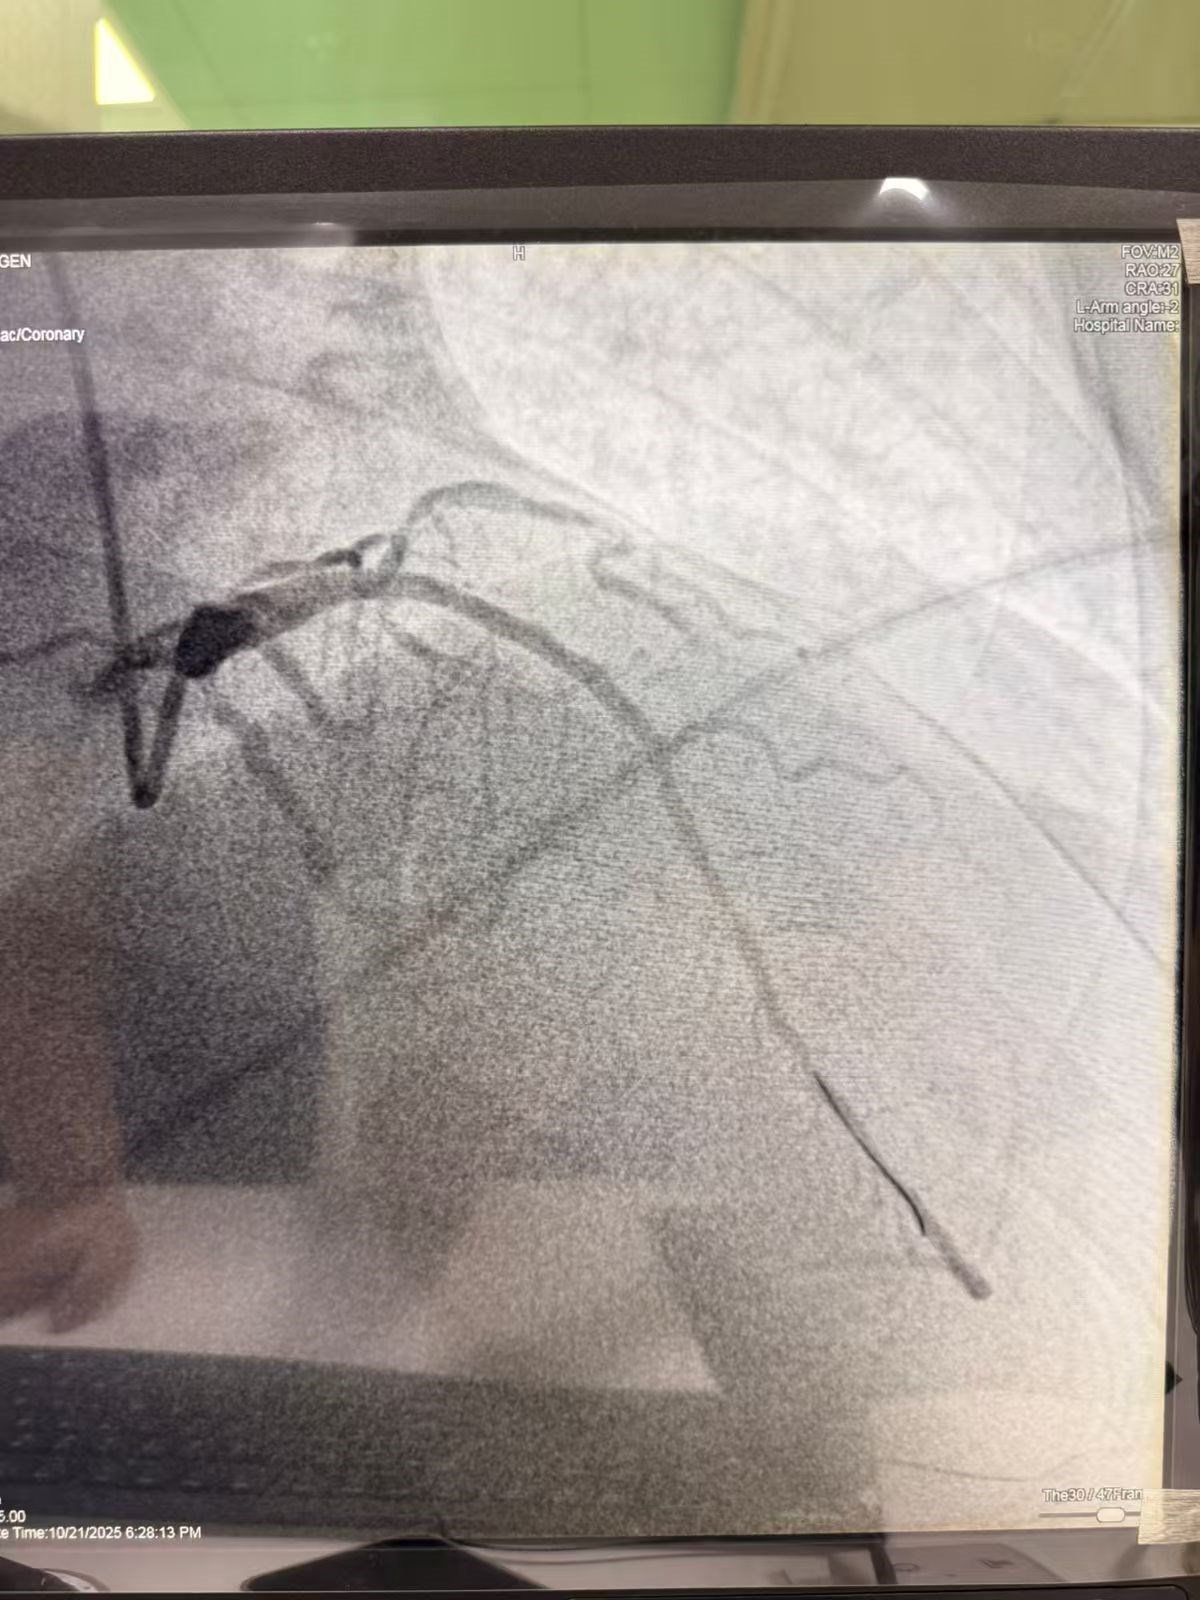

ຜົນການກວດຢືນຢັນຄວາມເຊື່ອກ່ອນໜ້າ: ຫຼອດເລືອດ LAD ທີ່ສຳຄັນທີ່ສຸດຂອງຫົວໃຈ ໄດ້ອຸດຕັນຢ່າງສິ້ນເຊີງ. ທ່ານ ຫຼູ ຊ່ານ ໄດ້ຊີ້ນຳແພດທ້ອງຖິ່ນ ໃຫ້ຜ່ານລວດນຳສົ່ງ, ຂະຫຍາຍດ້ວຍບານ ແລະວາງໂຄງ Stent ໃນຈຸດທີ່ອຸດຕັນ ເຮັດໃຫ້ຫຼອດເລືອດທີ່ອຸດຕັນ ເປີດຂຶ້ນ, ສາມາດຟື້ນຟູການໄຫຼວຽນຂອງເລືອດ ໄປຫາກ້າມເນື້ອຫົວໃຈ, ຂັ້ນຕອນການຜ່າຕັດດຳເນີນສຳເລັດ. ອາການເຈັບຊື່ໜ້າເອິກຂອງຜູ້ປ່ວຍຫາຍໄປໃນທັນທີ ແລະ ຫຼັງຜ່າຕັດ, ຜູ້ປ່ວຍຟື້ນຕົວຢ່າງດີ ໃນການດູແລຂອງທີມແພດ ແລະ ສາມາດກັບໄປບ້ານໄດ້ພາຍໃນ 5 ວັນ.